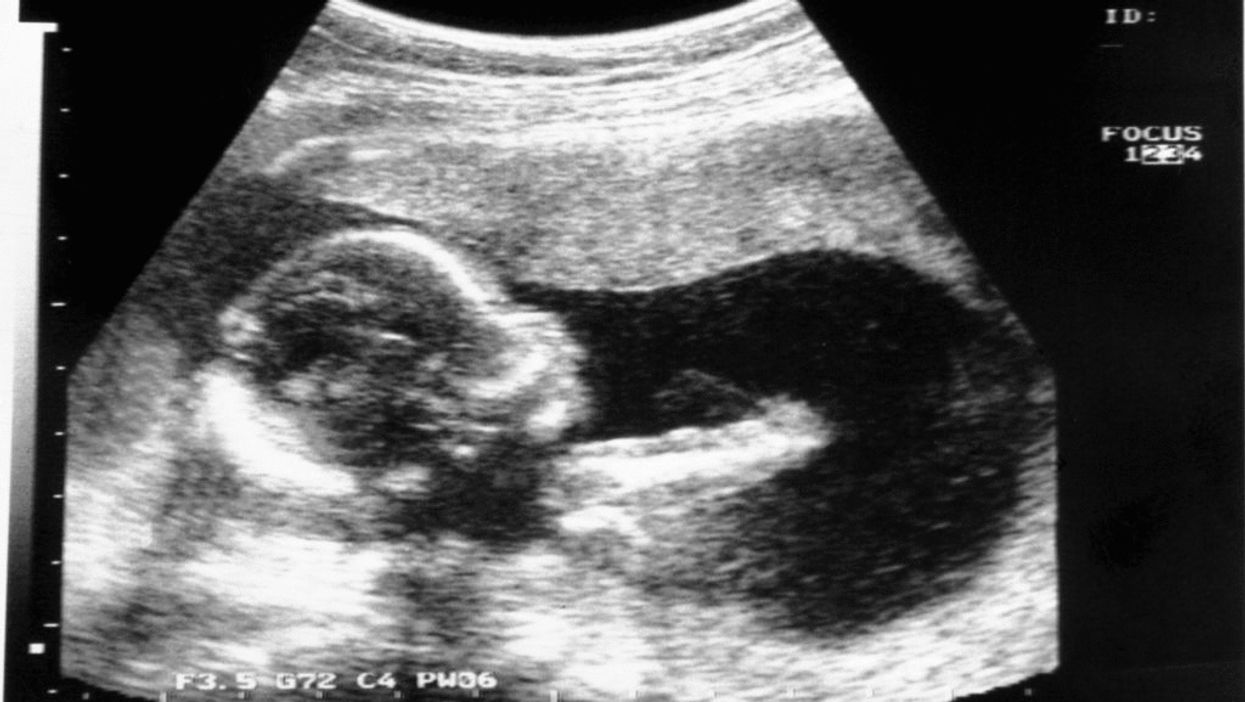

Medical consensus has believed that unborn babies do not feel pain until the middle or end of the second trimester, 20 to 24 weeks. But newly published medical research indicates that unborn babies can feel pain much sooner.

The new research indicates that unborn babies can feel "something like pain" as early as 13 weeks, pro-choice British pain expert Stuart Derbyshire — who has previously consulted Planned Parenthood — and American Dr. John Bockmann told the Daily Mail.